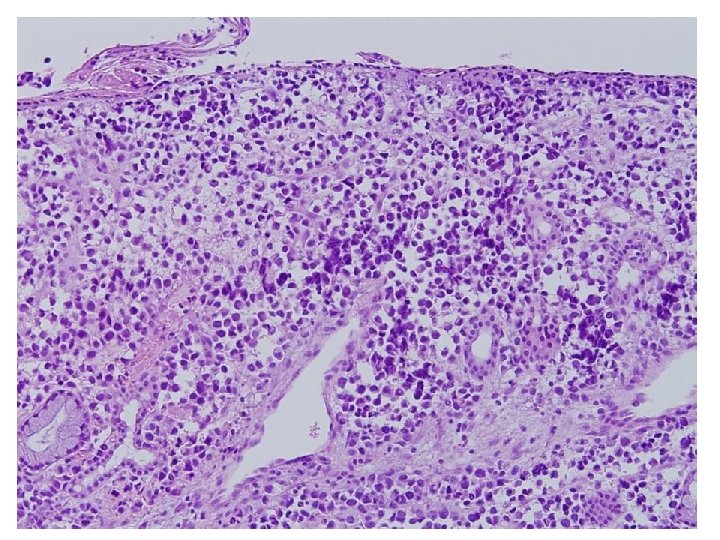

Cytologic features • Cellularity : High • Background : Clear, but necrotic cytoplasmic materials • Dispersed isolated round cells • Cytoplasm : dense, well defined border • Nucleus : small, eccenteric, round or curved, hyperchromatic • Mulinucleated, and binucleated cells • Nucleoli : indistinct, occasionally small nucleoli • Mitosis

Rhabdomyosarcoma • • • High cellularity Small round cell Rhabdoid feature Eccentric hyperchromatic nucleus Occasionally small nucleoli

Diagnosis FNA from left level Ⅲ lymph node : Metastatic rhabdomyosarcoma, alveolar type